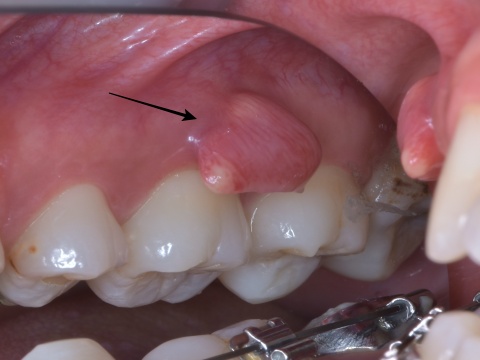

すると吸収部にはただ単に歯が溶けているのではなく、肉芽という歯茎の一部が入り込んでしまっているので、穴を開けた瞬間に血が噴き出してきて、血まみれで中を見るのが困難な状態でした。

この後歯茎を開いて、はみ出したMTAセメントと除去しきれていない外部吸収部を除去して、グラスアイオノマーというセメントにより同部を埋めました(赤矢印)。

これも言葉にして書くと簡単なのですが、これをピッタリ埋めるのが非常に難しかったです。